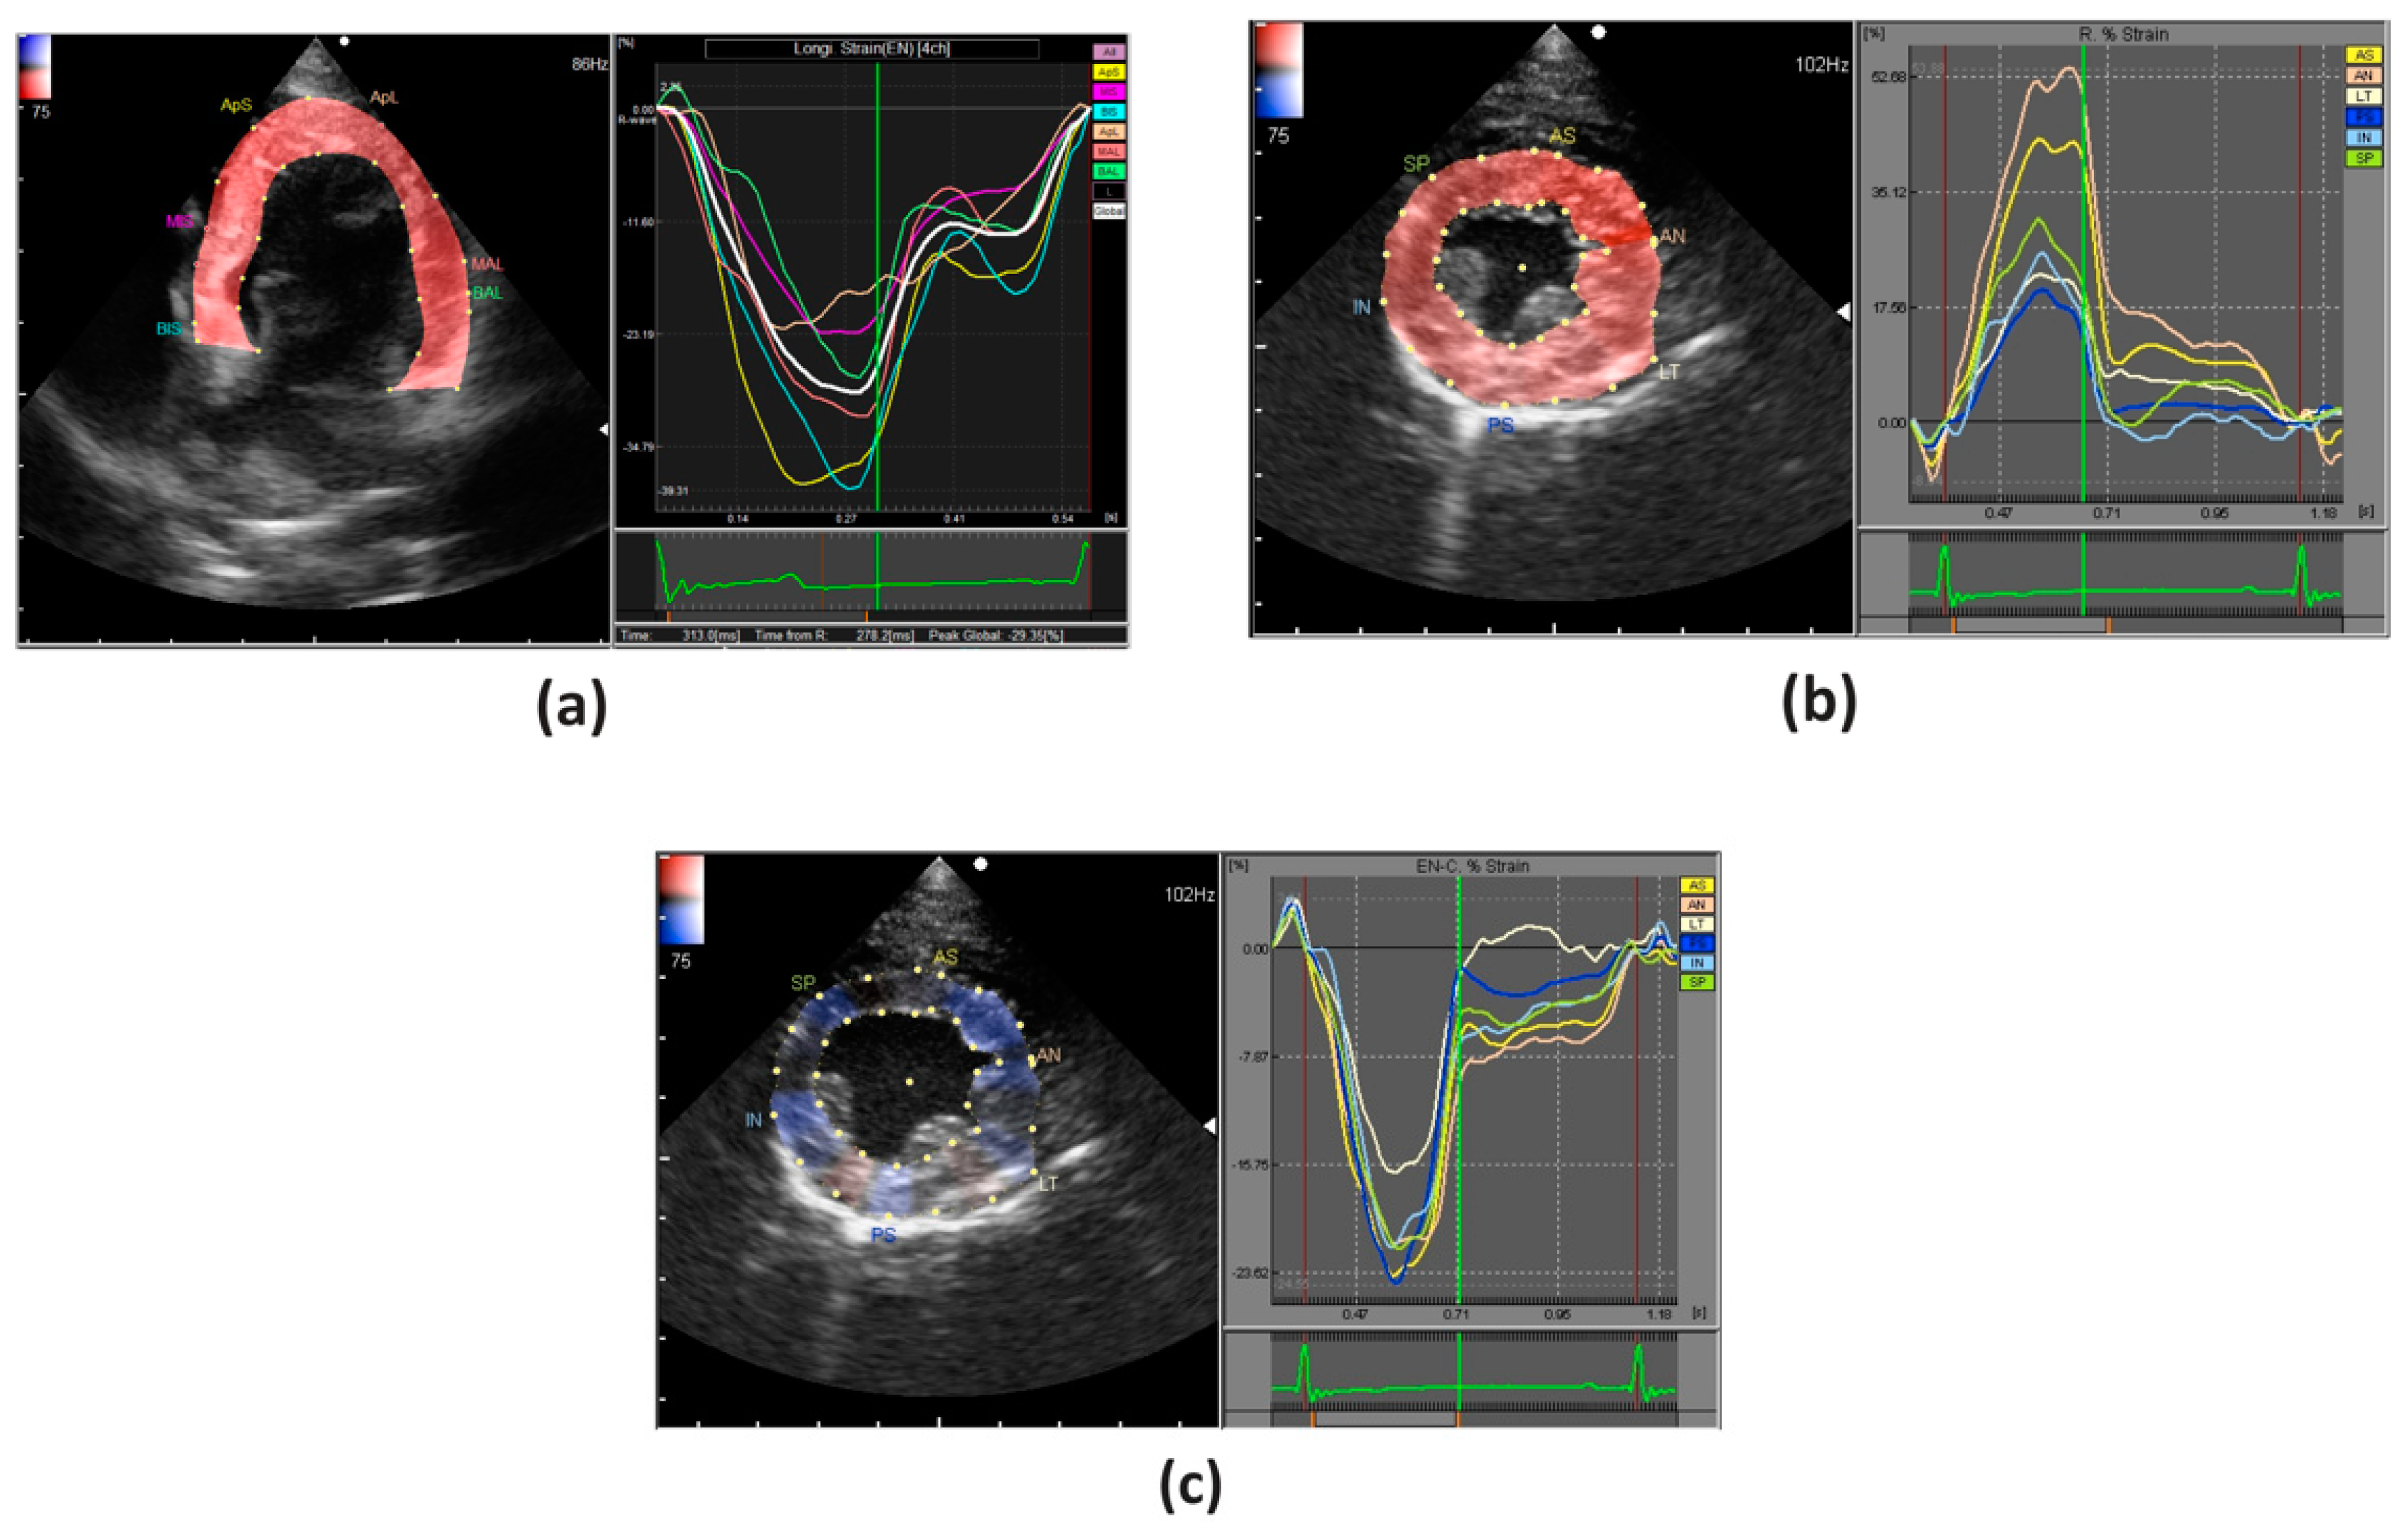

4.1. Longitudinal Deformation

4.2. Radial & Circumferential Deformation

4.3. Rotational Deformation